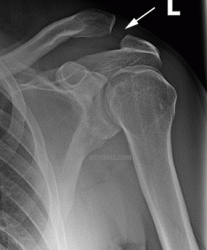

b. Following surgery to stabilize the joint with a 'twin-tail' tight-rope